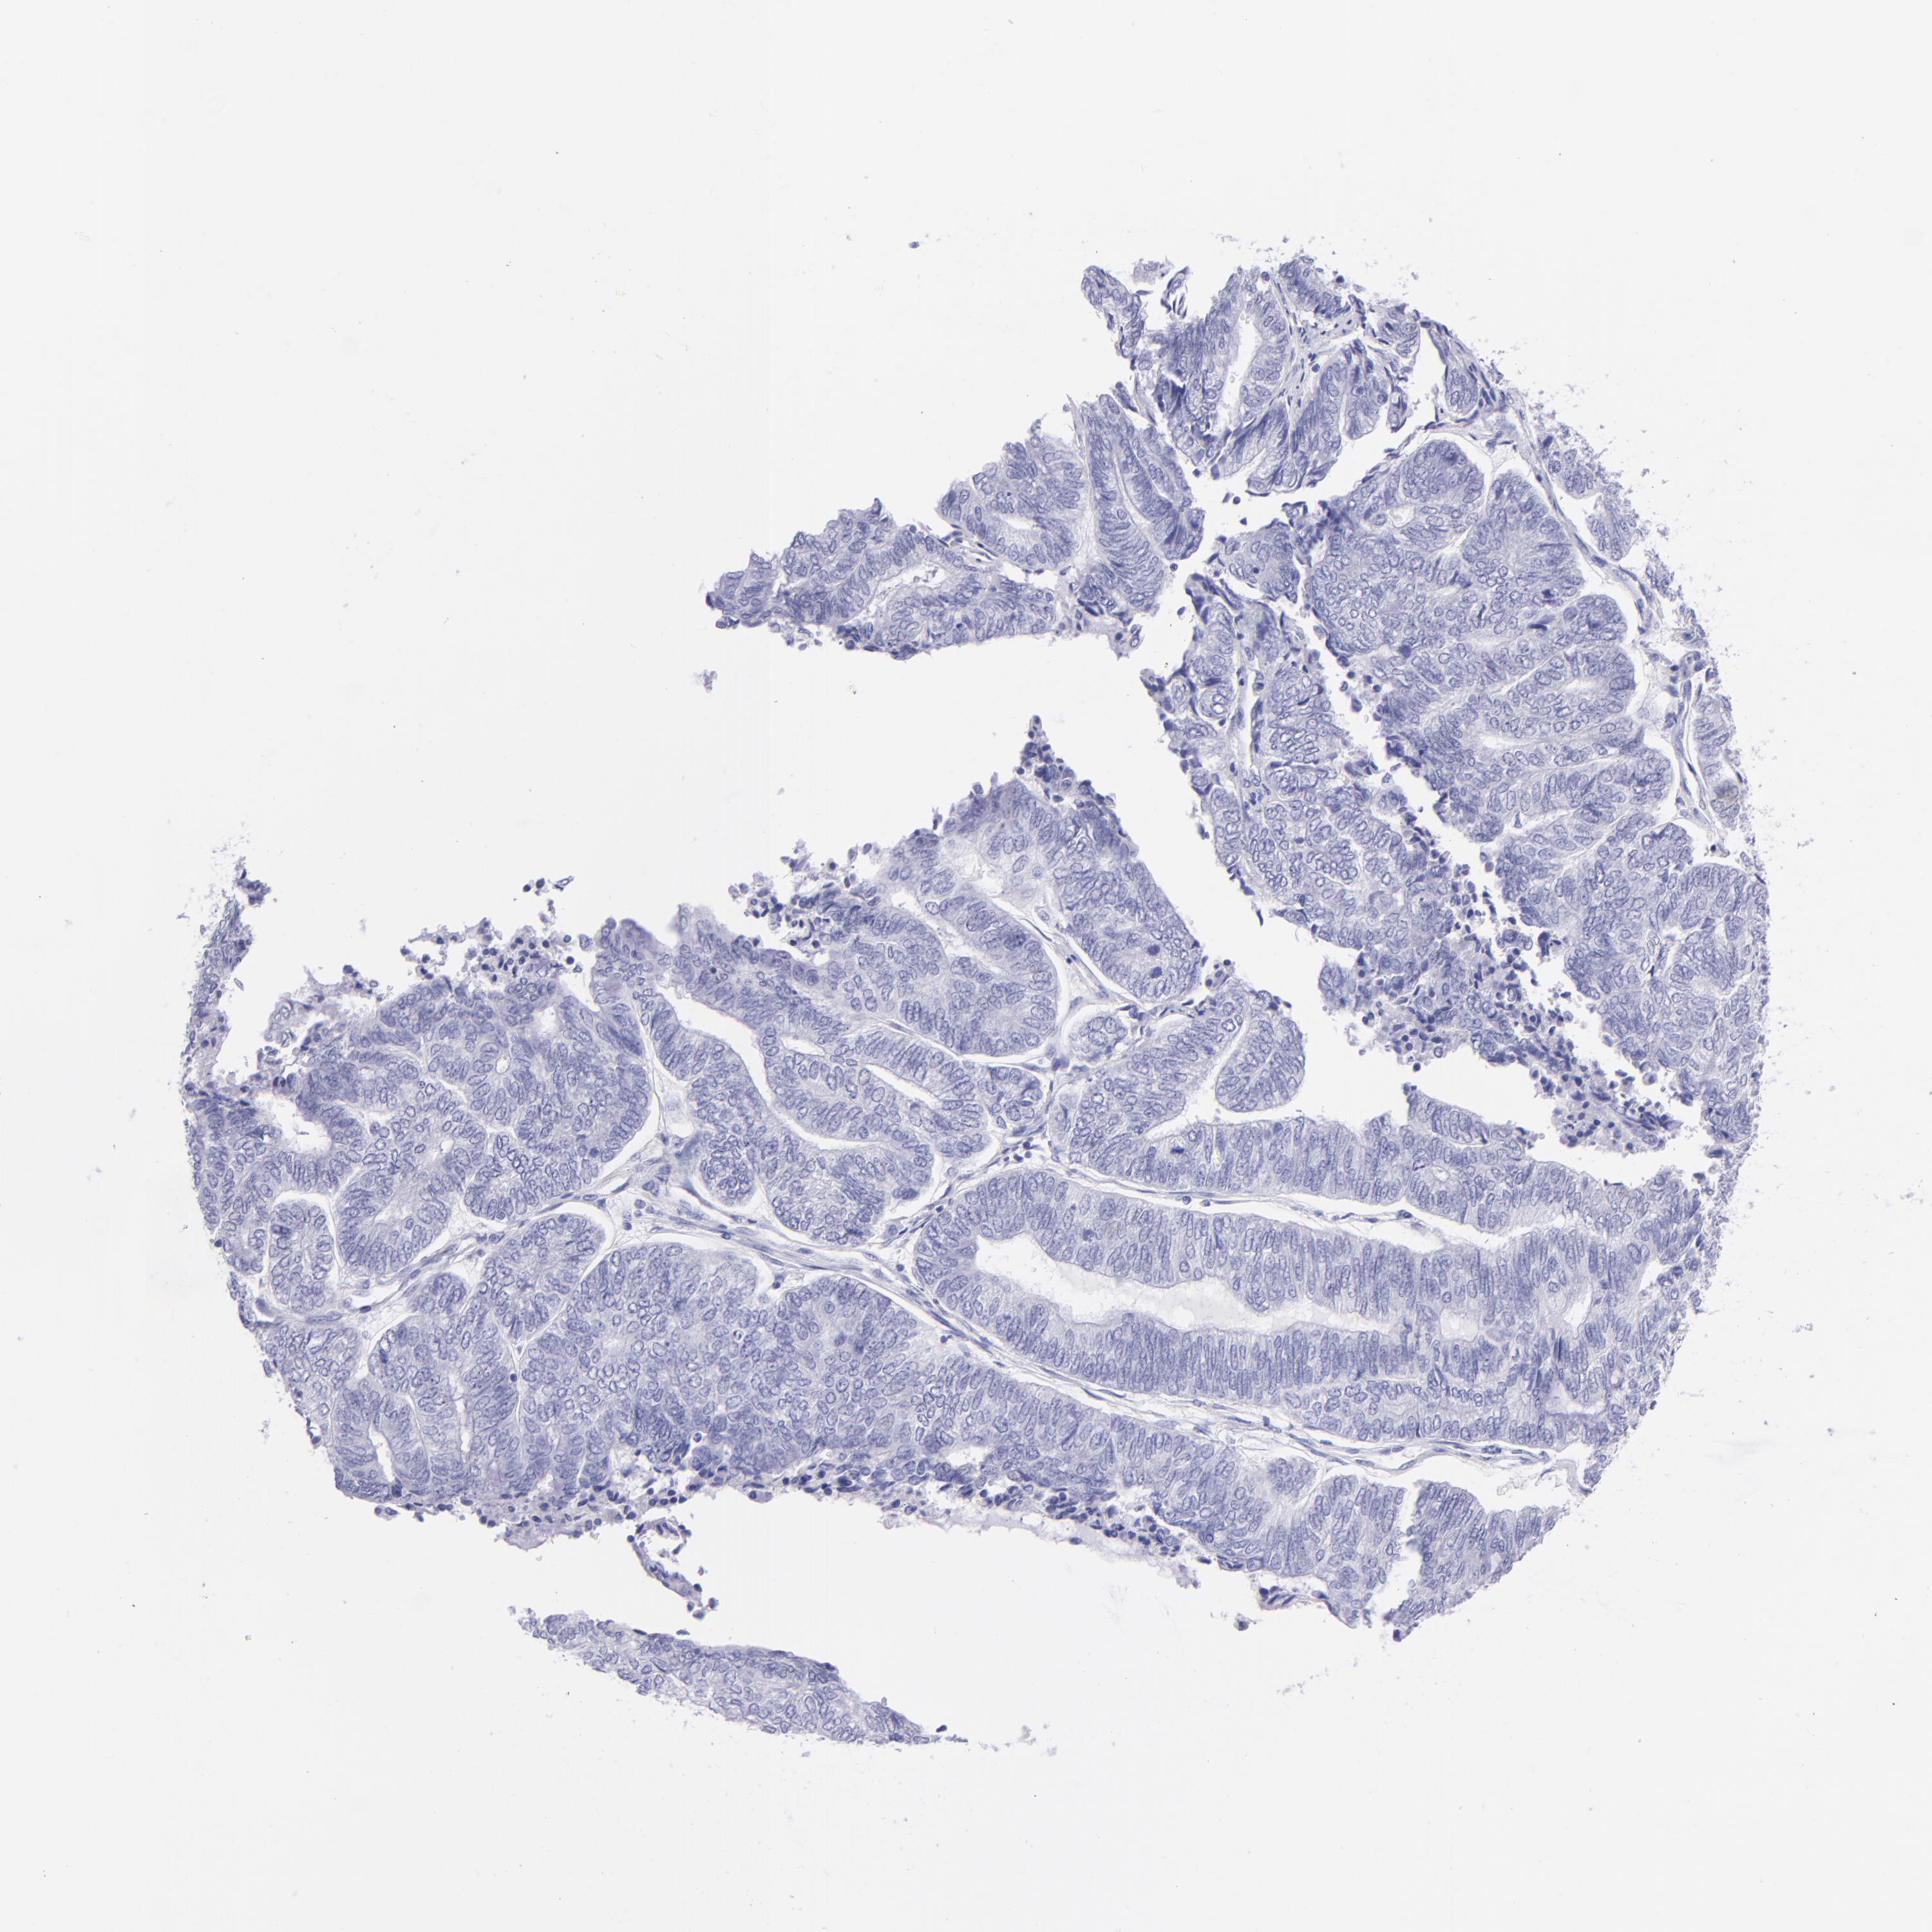

ENDOMETRIAL CANCER - Protein expressioni

A mouse-over function shows sample information and annotation data. Click on an image to view it in a full screen mode. Samples can be filtered based on level of antibody staining by selecting one or several of the following categories: high, medium, low and not detected. The assay and annotation is described here.

Note that samples used for immunohistochemistry by the Human Protein Atlas do not correspond to samples in the TCGA dataset.

Antibody stainingi

Antibody staining in the annotated cell types in the current human tissue is reported as not detected, low, medium, or high, based on conventional immunohistochemistry profiling in selected tissues. This score is based on the combination of the staining intensity and fraction of stained cells.

Each image is clickable and will lead to virtual microscopy that enables deeper exploration of all samples and also displays staining intensity scores, fraction scores and subcellular localization as well as patient and tissue information for each sample.

Antibody HPA009177

Antibody CAB002661